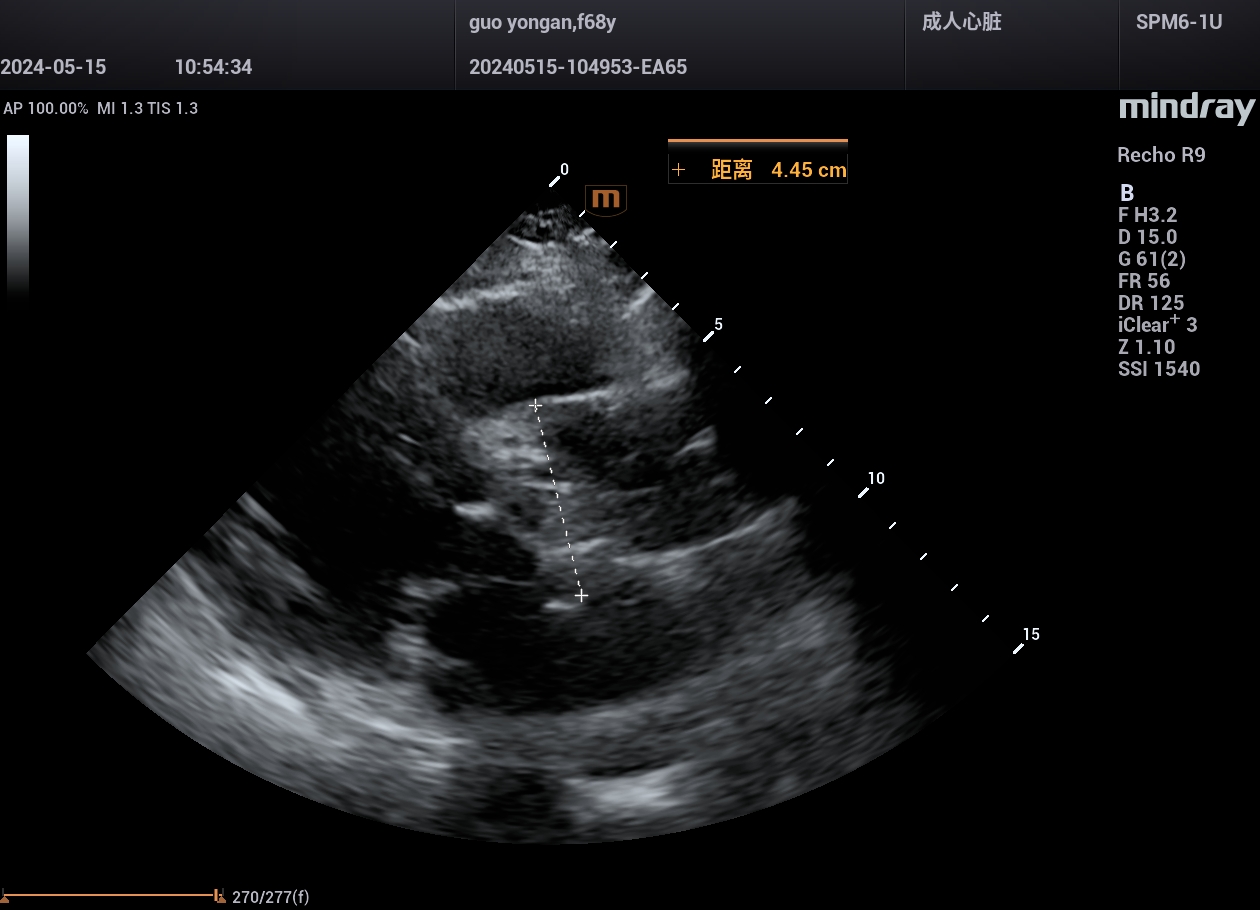

病例,急性心肌梗死,并发室间隔穿孔,迈瑞心脏彩超鲲鹏Recho R9,2024年5月

来源玉林市第一人民医院超声科,迈瑞超声鲲鹏实现超声事业高质量发展